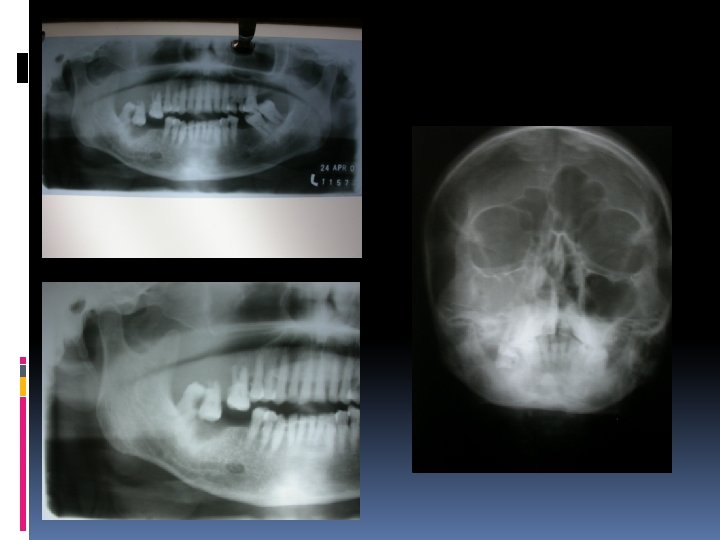

Imaging PA Mandible, Opg, Occlusal, PNS CT-Scan MRI Radio-nuclide scanning Chest PA